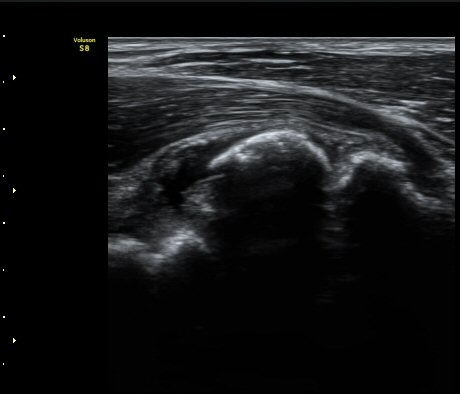

[ÆÈ²ÞÄ¡] ÆÈ²ÞÄ¡ °üÀý³» À¯¸®Ã¼¿¡ ÀÇÇÑ ÆÈ²ÞÄ¡ ÅðÇ༺ °üÀý¿°

¼ºº° / ³ªÀÌ

³²ÀÚ/ 44¼¼

ÁÖÁõ»ó

ÆÈ±ÀÄ¡ ÅëÁõ

ÃÊÀ½ÆÄ °Ë»ç